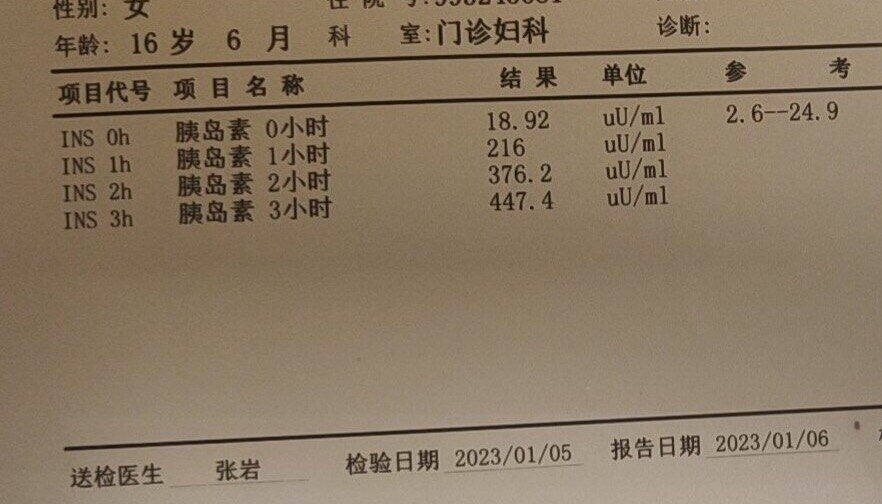

糖耐量受损和高同型半胱氨酸血症

胰岛素抵抗

维生素D缺乏

这是一位16岁的高中生,12岁初潮,月经不规律,这次是因为闭经四年前来就诊。根据她的病史症状、一系列化验和超声检查结果,我给她下的诊断是:糖耐量受损,胰岛素抵抗,高同型半胱氨酸血症,青春期多囊卵巢综合征。她的25羟基维生素D只有14.45ng/ml,所以我还诊断她维生素D缺乏。

这个才16岁的花季少女,她的同型半胱氨酸这么高(≧10μmol/L为高血同),估计她的动脉粥样硬化已经起步n年了。如果现在不开始加以控制的话,估计她在40岁左右就会出现心梗或脑梗。